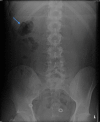

Abdominal pain secondary to intussusception is a common presentation in the paediatric population but rare in adults. Diagnosis is often difficult due to non-specific signs and symptoms. Adult intussusception presents more insidiously with intermittent abdominal pain and signs and symptoms of an acute abdomen are rare. In children, the aetiological factor is usually idiopathic, whereas intussusception in adults is more commonly due to an underlying pathology giving rise to a lead point. Consequently the treatment of choice is different-while it is supportive in children, surgical management is typically indicated in adults. In addition, the causes of a lead point precipitating adult intussusception are different depending on whether they arise from the small or large bowel. This report presents a case of jejunal intussusception in a 30-year-old man with a characteristic CT scan who required exploratory laparotomy and small bowel resection.